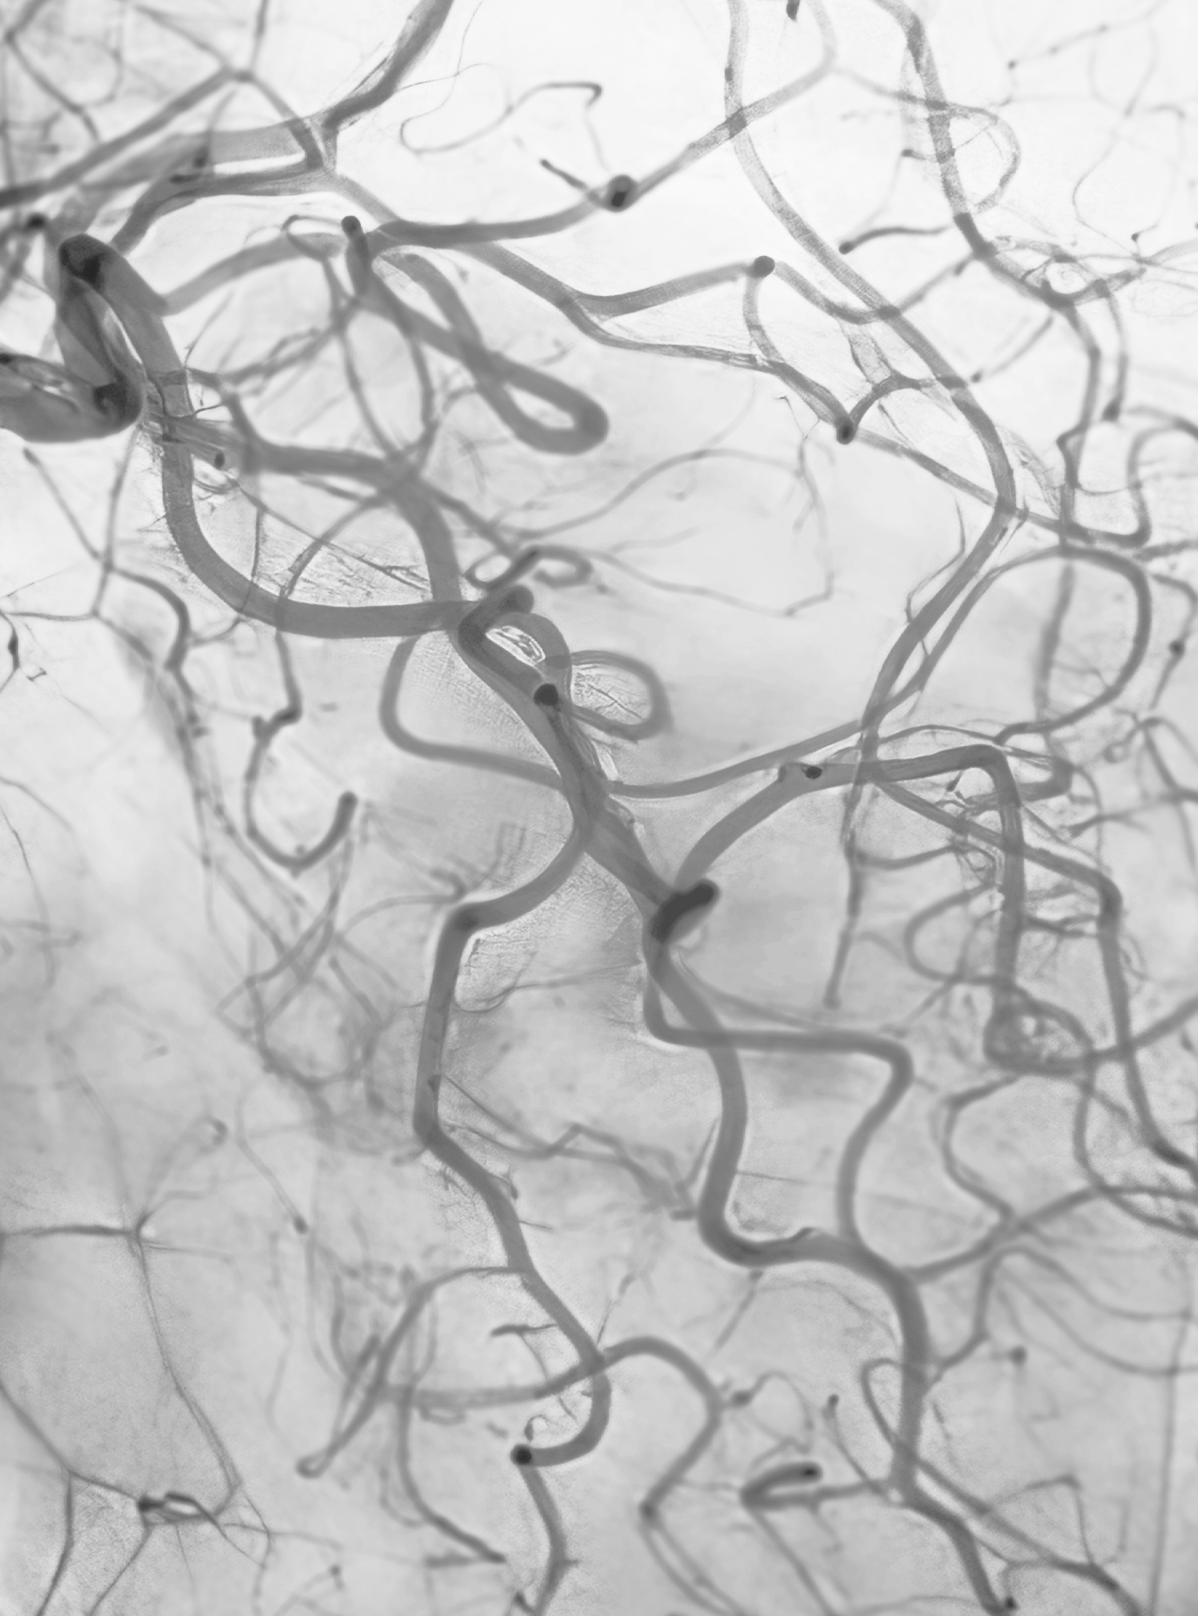

눈에 띄는 붉은 핏줄, 퍼져 있는 얇은 실핏줄처럼 보이는 혈관으로

이는 표피 바로 아래 모세혈관이 비정상적으로 확장된 상태입니다.

모세혈관 확장증 (거미혈관)

하지정맥류와 어떤 관계가 있나요?

다리(종아리, 허벅지)에 나타나는

모세혈관 확장증(붉거나 푸른 실핏줄)은

단순히 피부 문제가 아닌

하지정맥류와 매우 밀접하게 연관되어 있습니다.

모세혈관 확장증은 겉으로 보기엔

실핏줄이 도드라져 보이기만 하지만

도플러(초음파) 검사 진행 시

하지정맥류의 초기 단계이거나

이미 하지정맥류가 진행되고 있는

경우가 높습니다.

거미혈관이 보인다면 피부 문제가 아닌

혈관 이상 신호일 수 있습니다.